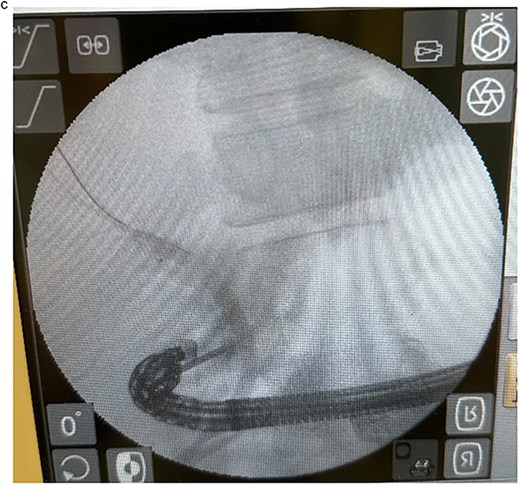

In view of the ongoing leakage and the hostile operative field, a third intervention was undertaken on postoperative day 24 following the second surgery. After multidisciplinary discussion, a combined surgical–endoscopic approach was undertaken in collaboration with internal medicine specialists. Intraoperative findings revealed dense adhesions from prior surgeries and a 0.5-cm perforation at the proximal duodenal stump, located near the ampulla of Vater. Initial endoscopic retrograde cholangiopancreatography (ERCP) was unsuccessful due to limited ampullary access; thus, EUS-CDS with ENBD placement was performed as an alternative strategy. From the duodenal bulb, the common bile duct (CBD) measured 4.7 mm on EUS, and Doppler confirmed no intervening vessels (Figs 4a and 4b). A 19-gauge EZ Shot 3 needle (Olympus) was used to puncture the extrahepatic bile duct, and bile aspiration followed by contrast injection confirmed correct positioning (Fig. 4c). A VisiGlide 2 angled guidewire (0.025 inch) was advanced into the right intrahepatic duct, and the tract was dilated using an ES dilator. A 7-Fr ENBD catheter was subsequently deployed across the choledochoduodenostomy under fluoroscopic guidance, achieving effective biliary drainage (Figs 4d and 4e). In addition, a 16-Fr Foley catheter was inserted into the duodenal perforation as a duodenostomy tube (Fig. 4f) for external drainage, and six closed wound vacuum drains were placed for peritoneal irrigation and drainage.